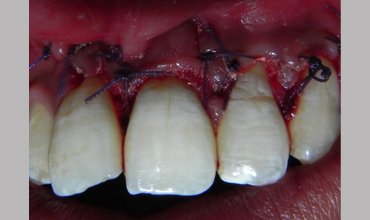

Periapical Surgery

Surgical Management Of Large Periapical Cyst